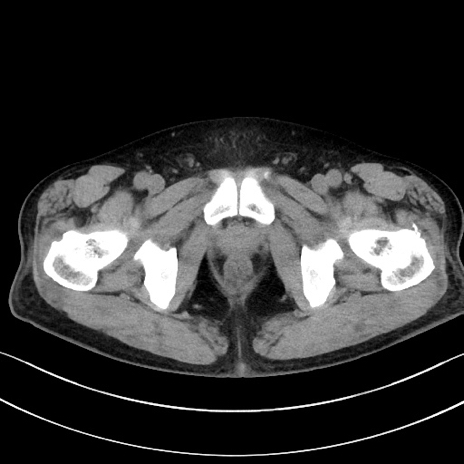

症例15(横断像)

【症例】70歳代男性

【主訴】腹痛

【現病歴】今朝から腹痛あり。全体的に痛い。特に左上の方。排ガスが今日はない。冷や汗が出る。

【既往歴】直腸癌術後

【身体所見】左側腹部〜上腹部に圧痛あり。腹膜刺激症状明らかなではない。軽度反跳痛。左下腹部に術後瘢痕あり。

【データ】WBC 7700、CRP 0.02